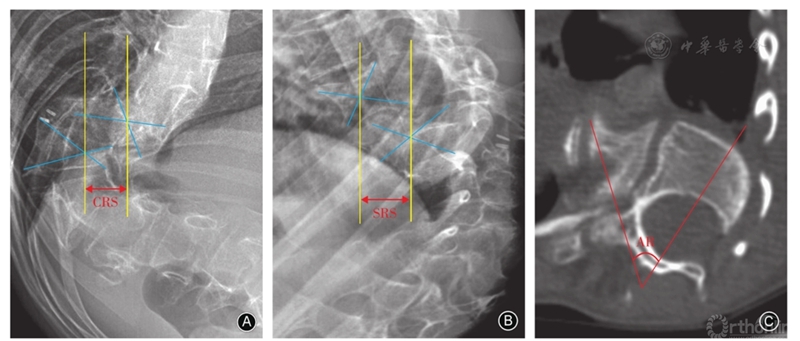

如上图中,该患者:A术前冠状面最大Cobb角测量值为56,横跨5个脊柱节段(T8-L1),每节段冠状面畸形角比(DAR)为11.20。B,术前矢状面最大Cobb角为88°,跨越6个脊柱节段(T7-L1),矢状面DAR为14.60。该患者的总DAR为25.8°/节段

本研究纳入了35例接受胸腰椎VCR矫形手的的儿童脊柱畸形患者。作者将MEP警报的定义是振幅下降大于基线振幅的50%定义为术中电生理信号异常。根据MEP神经监测结果,将人群分为2组:信号异常组及对照组,进行对比分析DAR数值是否可以用来预测术中电生理信号异常的发生率。

高手术风险患者:MEP发生改变的几率高于75%;低手术风险患者:MEP发生改变的几率低于25%。基于多因素回归分析,S-DAR得分高于22°或T-DAR得分高于45°患者为高手术风险组。此外,在此模型下,术中电生理异常的发生率的随着S-DAR的增加而显著增加。矢状DAR大于28°时为90%,矢状DAR大于32°时为95%。